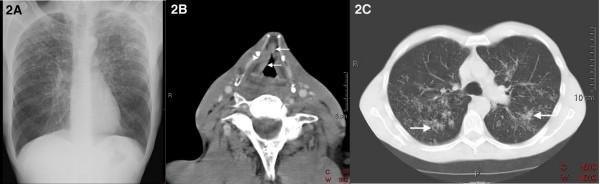

We describe the case of a 50-year-old Caucasian man who presented with the clinical picture of laryngeal cancer, but which turned out to be tuberculosis. We illustrate the difficulty of recognizing laryngeal tuberculosis both clinically and even with radiological examination.